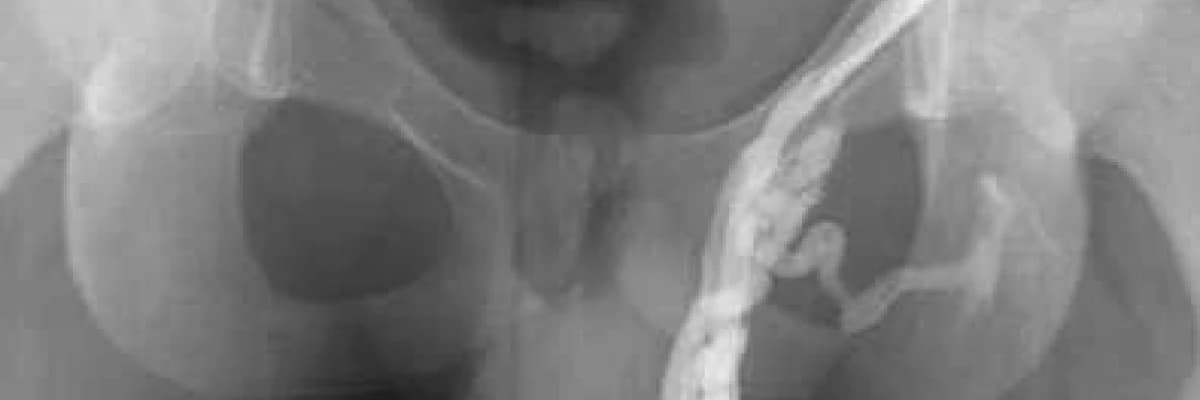

Varikoselin bugün için tedavisi cerrahidir. Mikrocerrahi ile spermatik ven ligasyonu adı verilen bir operasyonla genişleme gösteren damarlar bağlanır. Bu operasyon endoskopik olarak yapılabileceği gibi radyolojik embolizasyon (radyolojik kontrol altında genişleyen damarı tıkayan bir madde enjekte edilmesi) teknikleri de kullanılabilir. Tekniklerin birbirleriyle karşılaştırmalı çalışmaları olmadığından hangisinin daha üstün olduğu konusunda kesin bir görüş birliği yok.

III. derecede ise damarlar çok genişlemiş, kıvrımlar çok büyük yumaklar yapmıştır gözle görülebilir ve bozulmuş dolaşıma bağlı testislerde ufalma görülebilir.